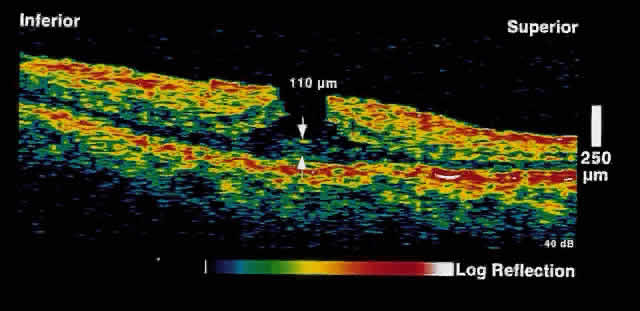

choriocapillaris/RPE layer.  Fig. 2. OCT image shows a neurosensory detachment secondary to central serous chorioretinopathy. The

difference in optical reflectivity between the posterior

boundary of the neurosensory retina and the underlying serous

fluid allows even small areas of elevation to be detected. Fig. 2. OCT image shows a neurosensory detachment secondary to central serous chorioretinopathy. The

difference in optical reflectivity between the posterior

boundary of the neurosensory retina and the underlying serous

fluid allows even small areas of elevation to be detected.